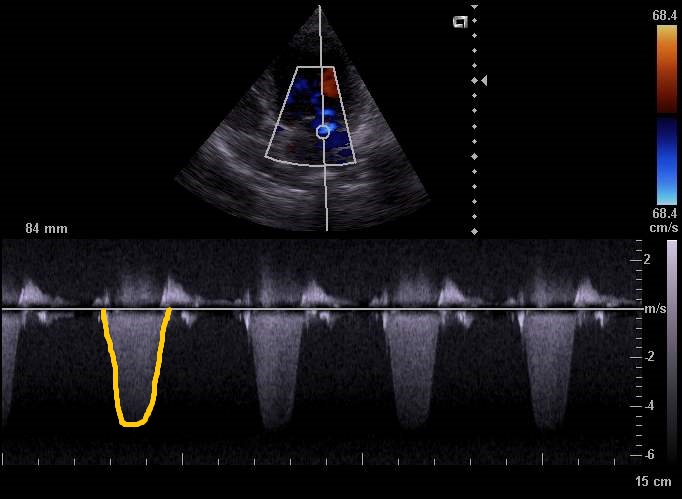

Osmiletý kříženec Sheldon byl u nás loni v květnu na pravidelné vakcinaci. Pan doktor pejska prohlédl a poslechl mu srdce. Z levé strany byl dobře slyšitelný šelest 2. stupně ze 6. Majitelům bylo pro jistotu doporučeno echokardiografické vyšetření (sono) srdce. Pro diagnostiku srdečního selhání lze využít EKG, rentgen hrudníku nebo sono. Posledně zmíněné vyšetření je nejpřesnější z hlediska zobrazení vnitřních struktur v srdci. Umožňuje posoudit chlopně, změřit vnitřní rozměry komor a síní a zhodnotit abnormality v proudění krve. Je to ale zároveň specializované vyšetření, které umí vyhodnotit pouze veterinární lékař – kardiolog.

Pacient zatím neměl žádné klinické příznaky, nekašlal ani nejevil známky únavy při větší aktivitě. Proto nás velmi překvapil nález na sonu. Sheldon měl těžkou nedomykavost mitrální chlopně, která byla úplně deformovaná a „netěsnila“ průchod mezi levou síní a komorou. To mělo za následek zpětný návrat krve z komory do síně, rozšíření síně, zesílení stěny komor – zkrátka velké přetížení srdce, které už nezvládalo tento stav kompenzovat. Co bylo ale nejhorší, městnáním krve v levé síni se vytvořil trombus (krevní sraženina), který vlál v proudu krve a hrozil utržením.

Pan doktor okamžitě nasadil léky na rozpouštění krevní sraženiny, na podporu srdeční stažlivosti a snížení krevního tlaku. Za 6 týdnů jsme s potěšením mohli konstatovat, že trombus byl plně rozpuštěn. Léčba pejska bude už doživotní, ale nebezpečí akutního selhání srdce nebo embolie trombu bylo pro tuto chvíli odvráceno.